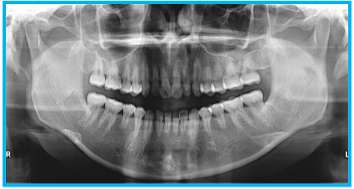

歯科パノラマ撮影

上下の歯列や顎の骨、顎関節などを一度に広範囲で撮影できる検査です。短時間・低被ばくで口腔全体の状態を把握でき、親知らずの位置や骨の異常、歯周病の進行度などの診断に有効です。